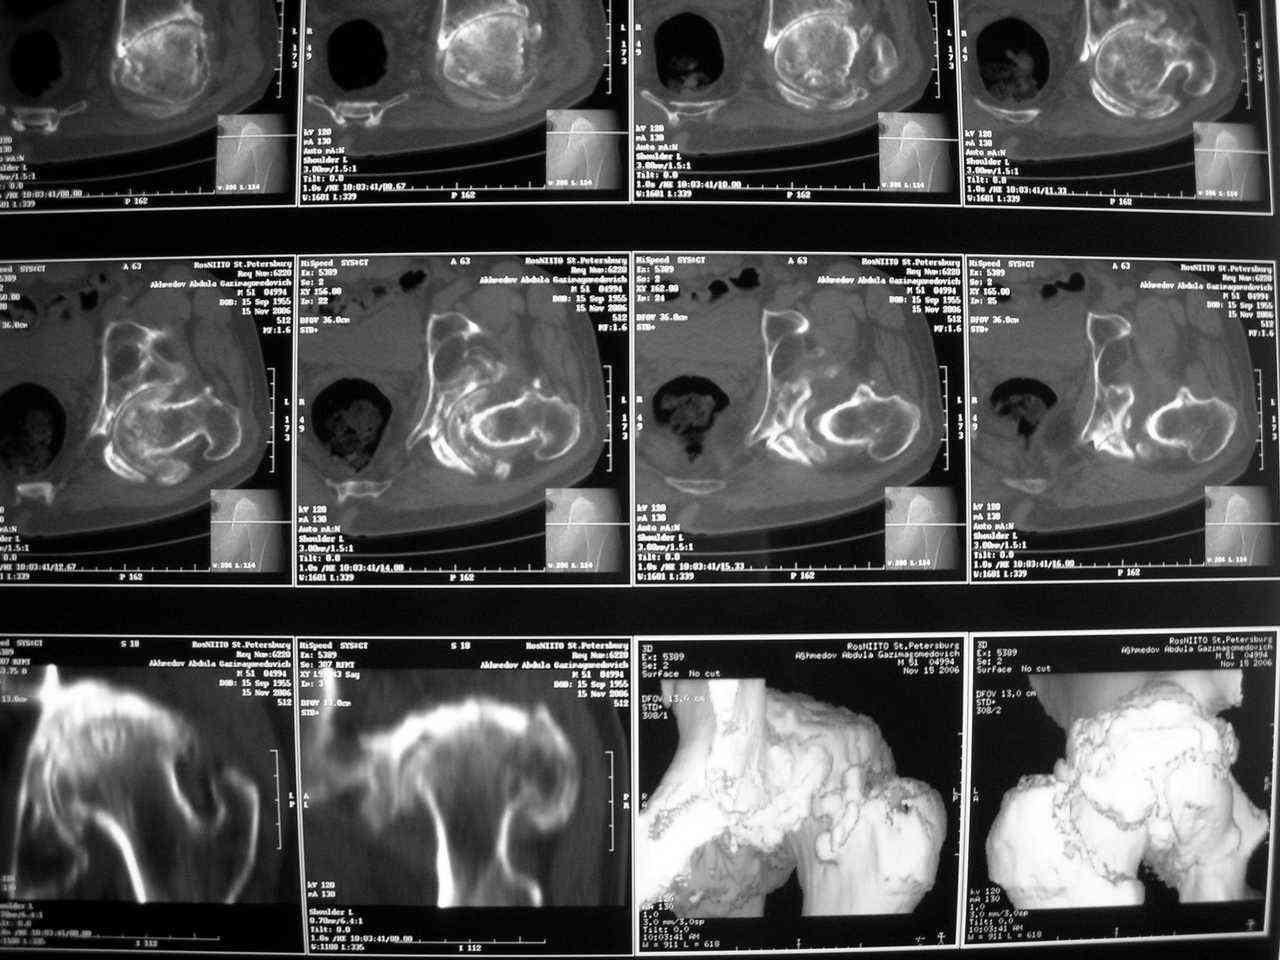

Еще одно наблюдение, неправильно сросшийся перелом заднего отдела ВВ с ввихом головки бедра 16-и летней давности.